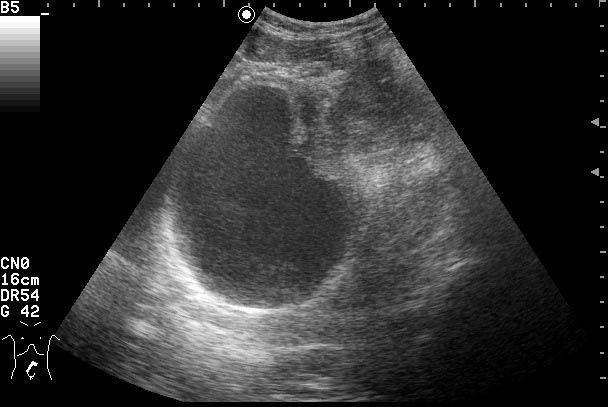

Клиническое выздоровление через 2 недели. Сонограммы мочевого пузыря через 6 недель:

Если бы это было воспаление кисты, то мы бы видели изначально кисту с акустически непрозрачным содержимым. После лечения мы бы видели кисту с анэхогенным содержимым.zubr писал(а):У Митькова аналогичное образование названо воспаление кисты урахуса,что в принципе суть не меняет,а предполагает аналогичную тактику.